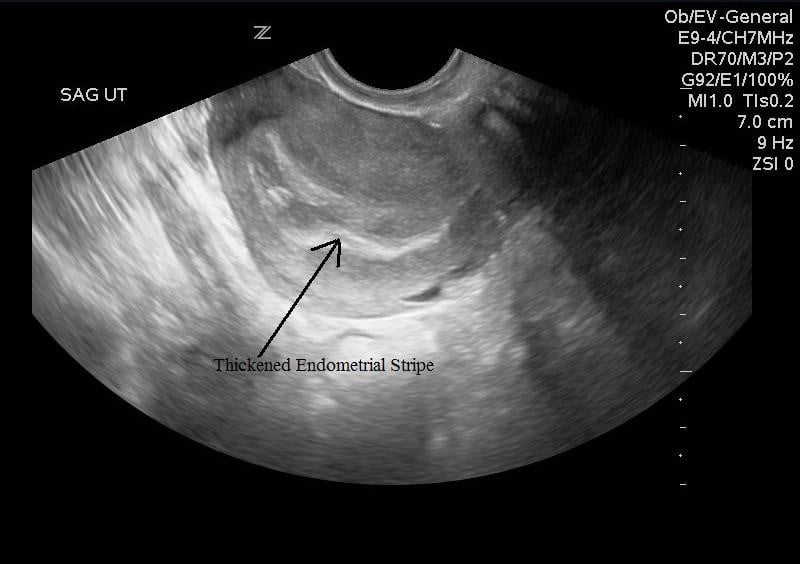

- Illustration 8. Image of transvaginal sagittal/longitudinal view. Notice hyperechoic (bright) endometrial stripe.

- Subchorionic Hemorrhage

- Frequent cause of first and second trimester bleeding19

- Anechoic/Hypoechoic crescent around gestational sac (Illustration 18)

- Illustration 18. Subchorionic hemorrhage